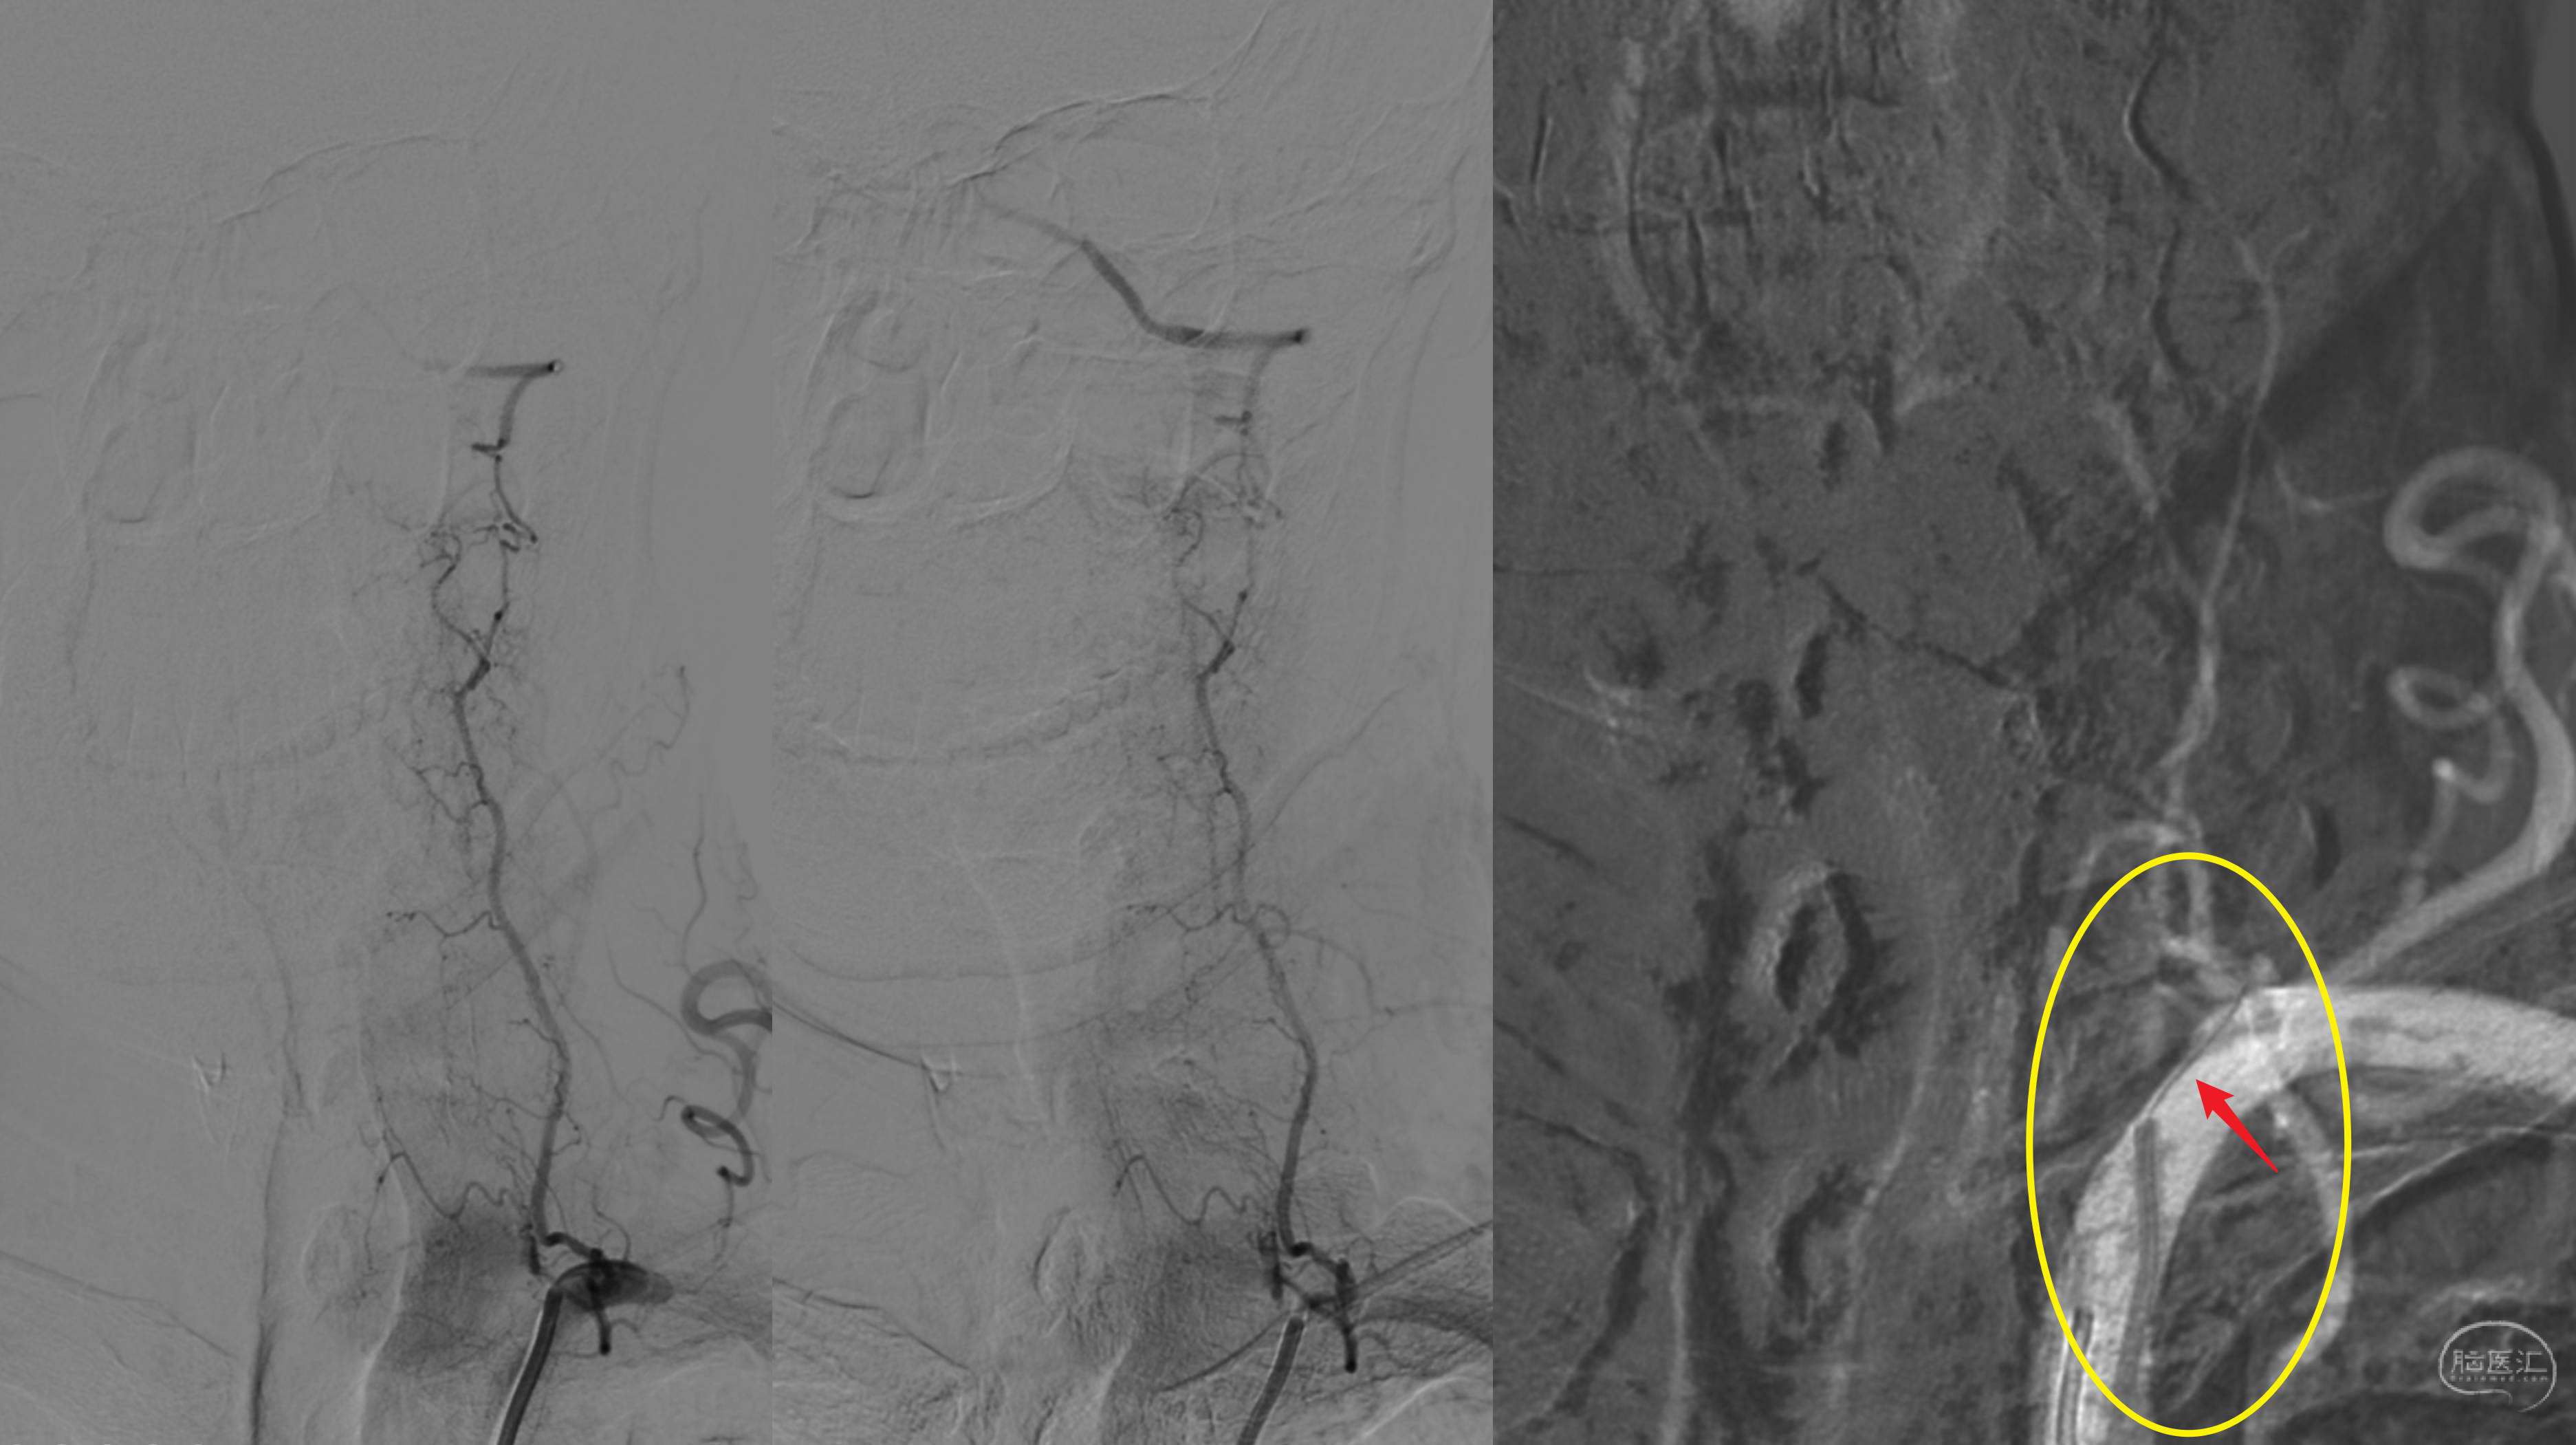

术后DWI未见新发梗塞。

后循环灌注改善!

复查DSA造影,提示桥血管通畅,后循环血流明显改善!